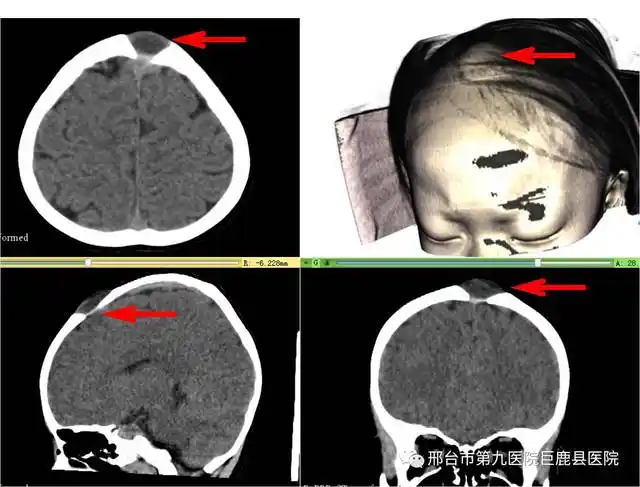

医院医护人员为熊先生进行ct扫描,采集头颅三维数据,进行三维重建设计

图2:来到我们昏迷促醒中心后我们给病人检查的头颅ct三维重建,为修补